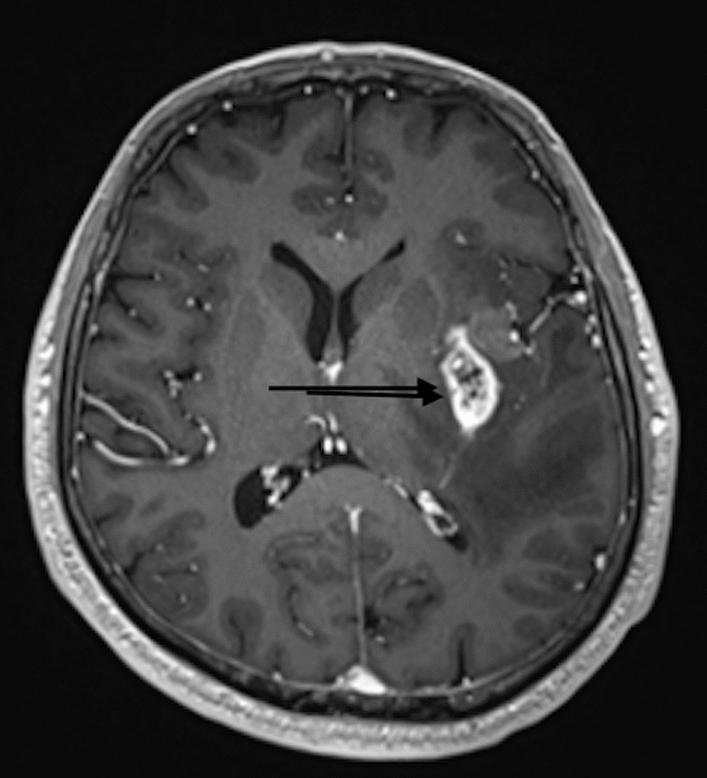

A 59-year-old Emirati man presented with intermittent sweating episodes and fatigue of 3 weeks duration. Initial differential diagnoses included poorly controlled diabetes, hyperthyroidism, and cardiac arrhythmia. A focal autonomic seizure was suspected after visits to five different specialities. A diagnosis of temporal glioblastoma was confirmed on an magnetic resonance imaging scan. The patient had surgical removal of the tumor, and his symptoms resolved after treatment with levetiracetam and dexamethasone.

一名59岁的阿联酋男性出现持续3周的间歇性出汗发作和疲劳症状。初步鉴别诊断包括控制不佳的糖尿病、甲状腺功能亢进和心律失常。在就诊于五个不同专科后,怀疑为局灶性自主神经发作。磁共振成像扫描确诊为颞叶胶质母细胞瘤。患者接受了肿瘤手术切除,经左乙拉西坦和地塞米松治疗后症状缓解。